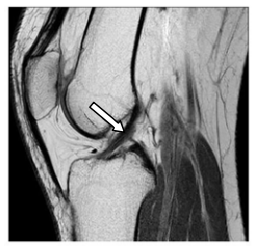

36 附圖所示為膝關節核磁共振成像(MRI)的矢狀切面,箭頭所指之黑色結構為何?

(A)半月板(meniscus) (B)肌肉(muscle) (C)十字韌帶(cruciate ligament) (D)側副韌帶(collateral ligament)